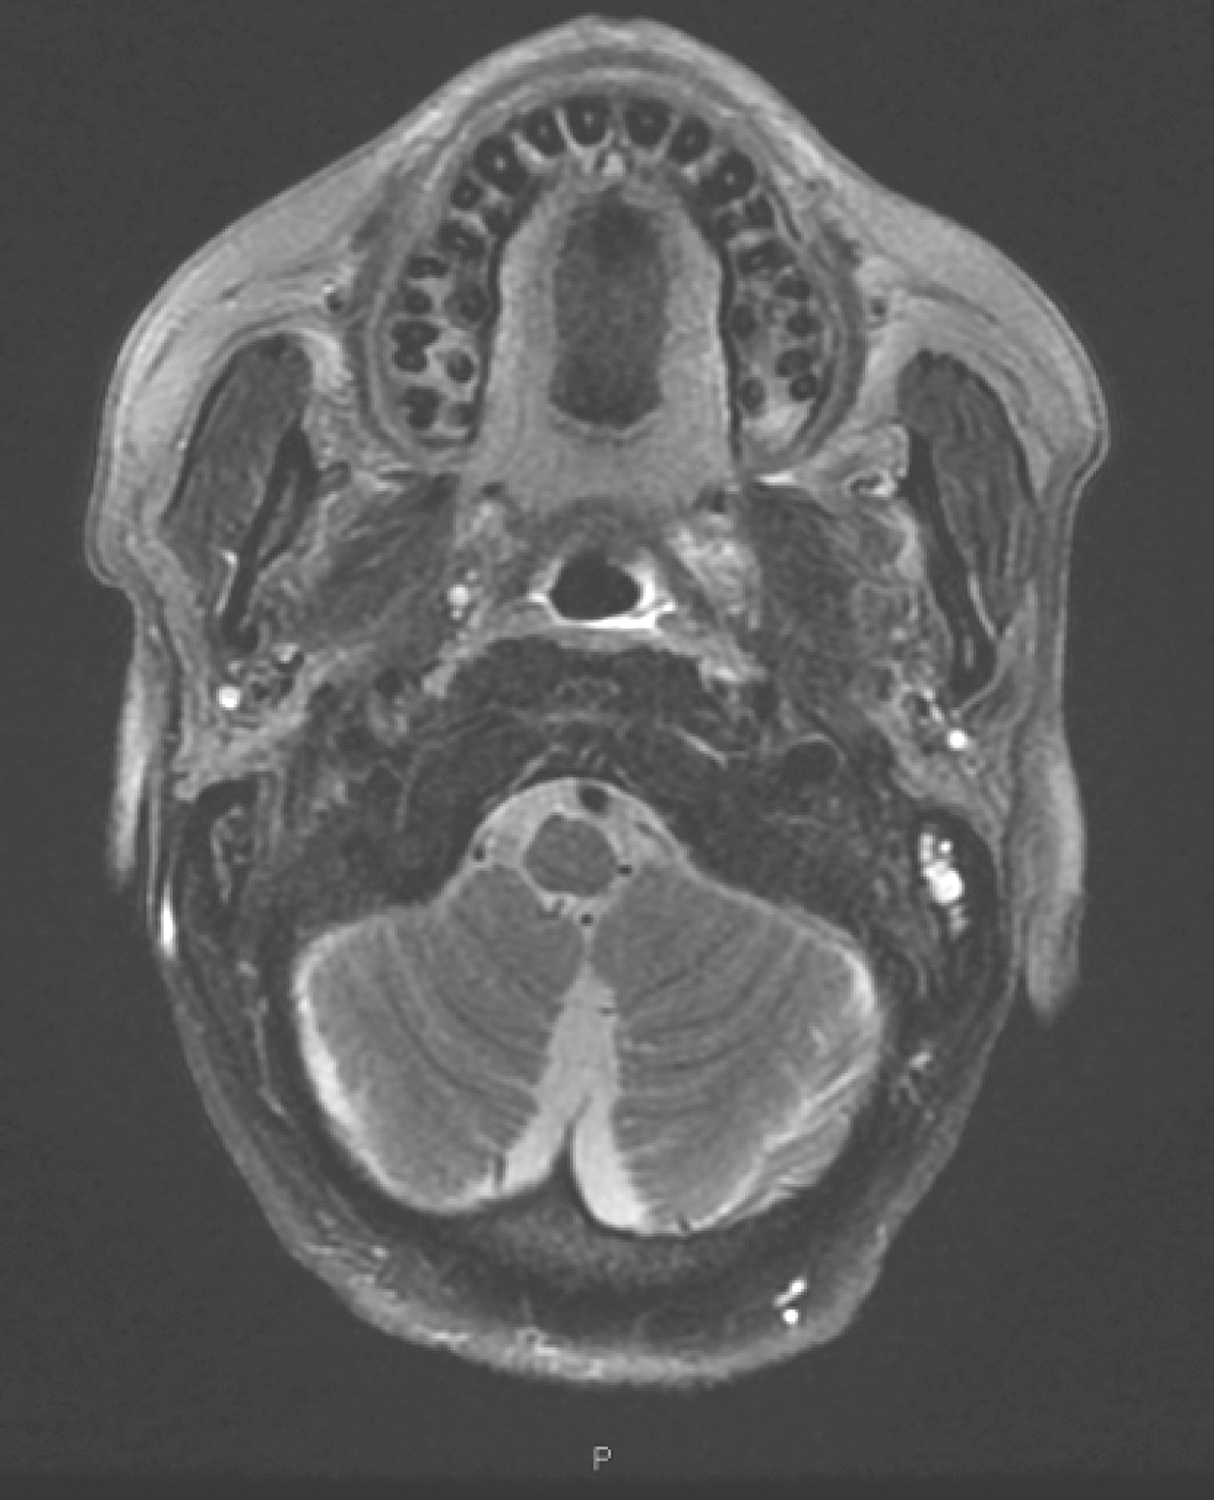

5.2016年10月19日口腔MRI

检查所见:

口咽左侧壁肿物,约2.3cm×1.8cm×2.3cm,T1WI呈等信号,T2WI/FS呈稍高信号,DWI扩散受限,增强扫描明显不均匀强化,肿物向外侵犯左侧咽旁间隙及左侧翼内肌,向下与左侧扁桃体关系密切(图4)。双侧颌下、颈深多发淋巴结,大者短径约0.8cm。

影像学诊断:

(1)口咽左侧壁肿物,考虑恶性,向外侵犯左侧咽旁间隙,贴邻左侧翼内肌,向下与左侧扁桃体关系密切。

(2)双侧颌下、颈深多发淋巴结,请随诊。

图4口腔MRI示口咽左侧壁肿物

4.疗中评估

(1)2016年12月13日口腔MRI检查:“口咽癌同步放化疗中”复查,与2016年10月19日MR图像比较:①口咽左侧壁肿物,较前缩小,现大小约1.9cm×1.0cm,T2WI/FS呈稍高信号,增强扫描不均匀强化,肿物向外侵犯左侧咽旁间隙及左侧翼内肌,向下与左侧扁桃体关系密切(图6),请继续随诊。②双侧颌下、颈深多发淋巴结,大者短径约0.7cm,请随诊。

图6复查口腔MRI示口咽左侧壁肿物较前缩小

2)2017年1月12日口腔MRI检查:

“口咽癌同步放化疗中”复查,与2016年12月13日MR图像比较,口咽左侧壁肿物较前缩小,现大小约1.5cm×1.0cm,T2WI/FS呈稍高信号,增强扫描不均匀强化,肿物向外侵犯左侧咽旁间隙及左侧翼内肌,向下与左侧扁桃体关系密切(图9),请继续随诊。双侧颌下、颈深多发淋巴结,大者短径约0.7cm,请随诊。

图9口腔MRI示口咽左侧壁肿物较前缩小

1.2017年3月16日口腔MRI检查

“口咽癌同步放化疗中”复查,与2017年1月12日MR图像比较:

(1)口咽左侧壁肿物现已显示不清,局部仅见口咽壁略增厚,T2WI/FS呈稍高信号,增强扫描中等强化,左侧咽旁间隙仍较模糊,并可见轻度强化(图10),上述请结合镜检并继续随诊。

图10口腔MRI示口咽左侧壁肿物现已显示不清,局部仅见口咽壁略增厚

(2)双侧颌下、颈深多发淋巴结,大者短径约0.5cm,请继续随诊。

4.2017年9月20日颈、口腔、口咽MR

与2017年3月16日MRI比较:

(1)左侧口咽壁略增厚,左侧咽旁间隙略模糊,未见具体肿物,考虑治疗后改变,同前相仿。

(2)双侧颌下、颈深多发淋巴结,大者短径约0.5cm,同前相仿,请继续随诊。